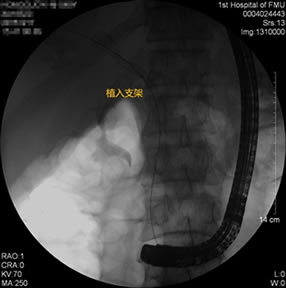

胃毕-Ⅱ术后乳头倒置 胃毕-Ⅱ术后胰管胆管双支架植入 胃毕-Ⅱ术后金属支架植入

胃毕-Ⅱ术后肝门部胆管狭窄 胃毕-Ⅱ术后金属支架植入

胃毕-Ⅱ术后胰管胆管双支架植入 胃毕-Ⅱ术后胆管金属支架植入